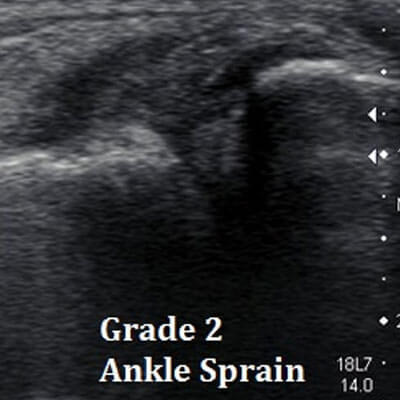

Ankle Sprain

Ultrasound is beneficial in diagnosis of soft tissue injuries including Plantar Fasciitis, Achilles Tendinopathy, Forefoot pathology, Ankle sprain